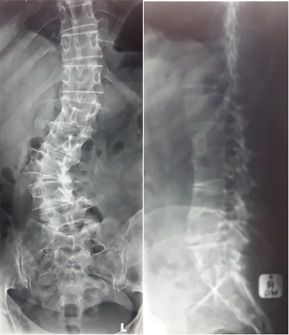

Degenerative scoliosis

Degenerative scoliosis is a result of wear and tear on the discs and joints of the spine. It is the most common type of scoliosis in adults, and usually happens in the lumbar (lower) spine.